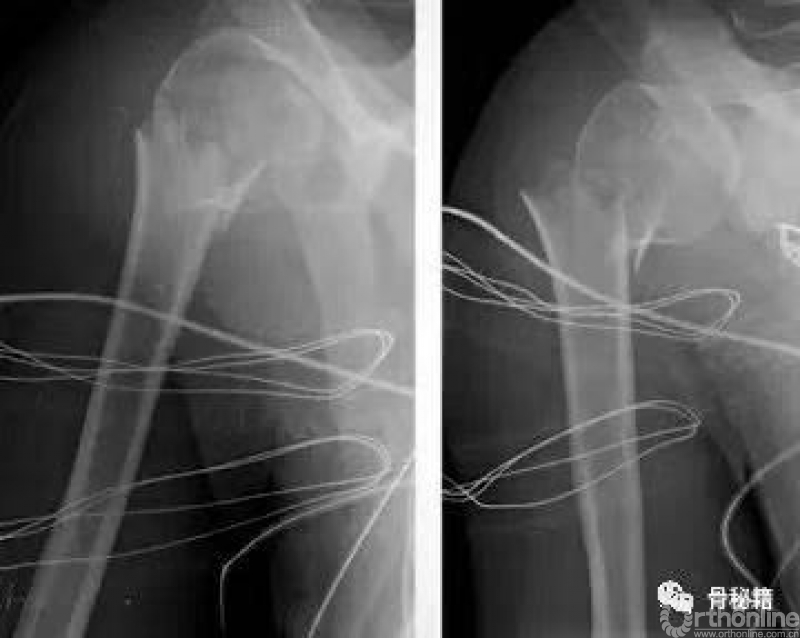

我们先看一个病例

这样一个病例你会选择钢板还是髓内钉?

钢板的风险:内侧肱骨距的骨折块难以复位,内侧失支撑

而髓内钉则不会害怕这样的问题

常用的克氏针的临时复位固定技术

可以应用大量的克氏针完成复位,

难复位的时候可以将头临时固定在关节盂上

最关键的就是剩余肱骨头需要进行外翻到合适的位置然后固定

将肱骨头的复位和合适的临时固定是最关键的